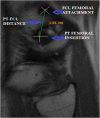

Fig. 1

Sagittal Magnetic Resonance Imaging (MRI) image showing method of measurement of PT-FCL distance.

Methods: The knee MRI data of 68 patients (43 males and 25 females) were studied. Measurement of PT-FCL distance was done in sagittal proton density fat-saturated (PDFS) sequence images. The femoral MLD and APD were measured in axial PDFS sequence images. The mean of each parameter was calculated and analyzed. To identify inter-observer agreement, we calculated Intra-Class Correlation Coefficient (ICC) for each parameter.

Results: The mean PT-FCL distance was 16.85 ± 1.55 mm (range 12.9-21.2 mm). In our observation, PT always inserts anteriorly and distally to FCL insertion on the lateral femoral condyle. The mean MLD was 78.74 ± 5.84 mm (range 65-90 mm). The Mean APD of the lateral femoral condyle was 60.47 ± 4.00 mm (range 52.5-69.5 mm). The difference between the mean values of all the above parameters in both genders was statistically significant (p-value <0.05). Inter-observer agreement was very good for measurement of PT-FCL distance (ICC 0.96), MLD (ICC 0.98) and APD (ICC 0.97).